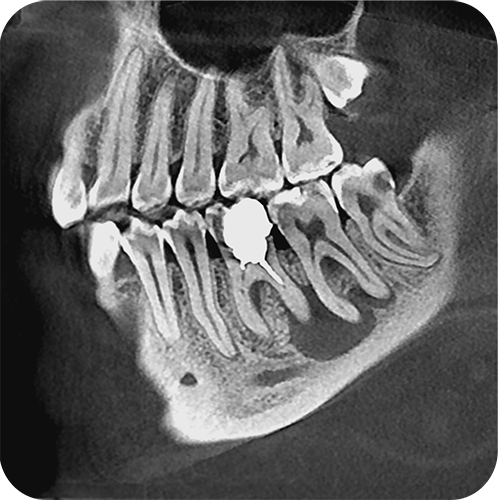

На выставке «Дентал Экспо Красноярск» успешно прошло заседание главных врачей во главе с Садовским Владимиром Викторовичем, Вице-президентом Общества Врачей России, Почетным Президентом СтАР, Директором Национального института исследований и адаптации маркетинговых стратегий (НИИАМС). Помимо насущных вопросов, руководители организаций региона обсудили преимущества и возможности использования стоматологического томографа Genoray Papaya 3D.

Несколько слов про преимущества:

- Плоскопанельный детектор имеет самую высокую в классе разрешающую способность